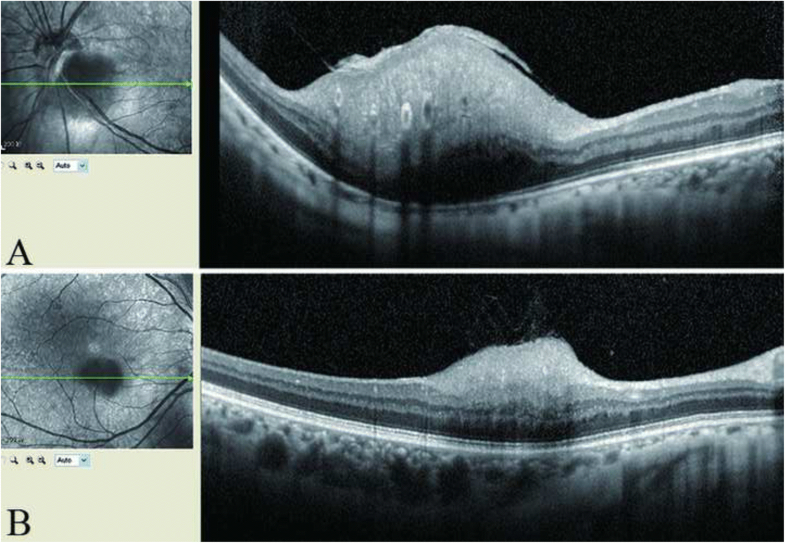

From www.jaapos.org

Everolimus to treat aggressive retinal astrocytic hamartoma in tuberous Tuberous Sclerosis Eye Findings To evaluate genotype/phenotype correlations in individuals with astrocytic hamartoma (ah) and retinal achromic patch (ap) in the setting of tuberous sclerosis complex (tsc). These manifestations include optic nerve hamartomas, elevated intracranial pressure, cranial. Tuberous sclerosis is a neurocutaneous disorder characterized by multiple benign tumors of the ectoderm. Retinal hamartomas are the most common ocular finding in tuberous sclerosis. Learn how. Tuberous Sclerosis Eye Findings.

From bmcophthalmol.biomedcentral.com

Retinal astrocytic hamartoma in tuberous sclerosis complex in an Tuberous Sclerosis Eye Findings These manifestations include optic nerve hamartomas, elevated intracranial pressure, cranial. To evaluate genotype/phenotype correlations in individuals with astrocytic hamartoma (ah) and retinal achromic patch (ap) in the setting of tuberous sclerosis complex (tsc). Learn how to diagnose tuberous sclerosis complex (tsc), an inherited neurocutaneous disorder with pleomorphic. Tuberous sclerosis is a neurocutaneous disorder characterized by multiple benign tumors of the. Tuberous Sclerosis Eye Findings.